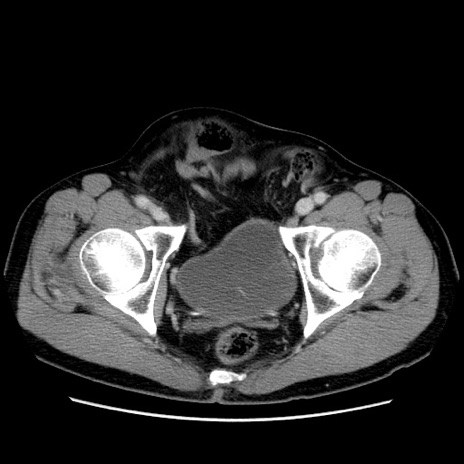

症例34(横断像)

【症例】60歳代 男性

【主訴】右鼠径部膨隆

【現病歴】1年程前より右鼠径部膨隆あり。自己にて還納可能だったため放置していた。3時間前より右鼠径部の脱出を認め、還納困難となり受診。

【既往歴】高血圧

【身体所見】右鼠径部に小児頭大の膨隆あり。弾性硬であり、用手還納は困難。左鼠径部にも膨隆を認める。脱出はなし。

【データ】WBC 15500、CRP 測定なし